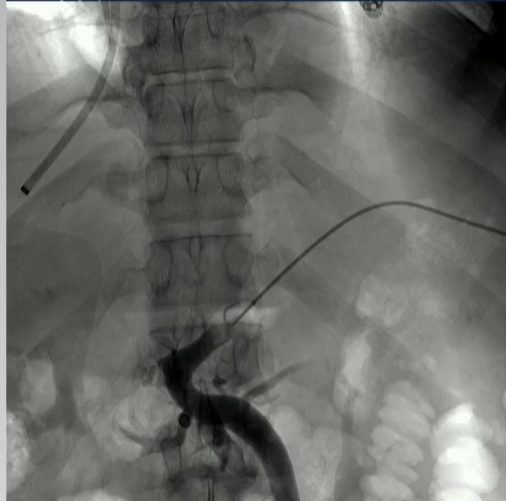

该程序包含以下步骤: 经脾脏入路:在超声引导下,刺穿脾静脉内的一个实质内分支。 在通过脾静脉造影确认了静脉通路后,导管和导丝被推进,以穿过脾静脉并抵达血栓化的门静脉。在门静脉/右门静脉分支处放置圈套器,为TIPS穿刺精准定位。TIPS穿刺圈套器,并穿过圈套器完成TIPS

步骤: 鉴于慢性血栓形成的复杂性: 一种经脾脏途径的门静脉再通术(PVR)。 随后是经颈静脉肝内门体分流术 。